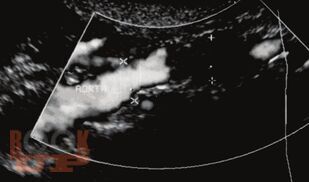

В монографии показаны ближайшие и отдаленные результаты бедренно-подколенного шунтирования в зависимости от вида трансплантата; представлена технология медицинской реабилитации пациентов. Особое внимание уделено послеоперационным осложнениям и методике лечения больных с окклюзионным поражением бедренно-подколенного сегмента.